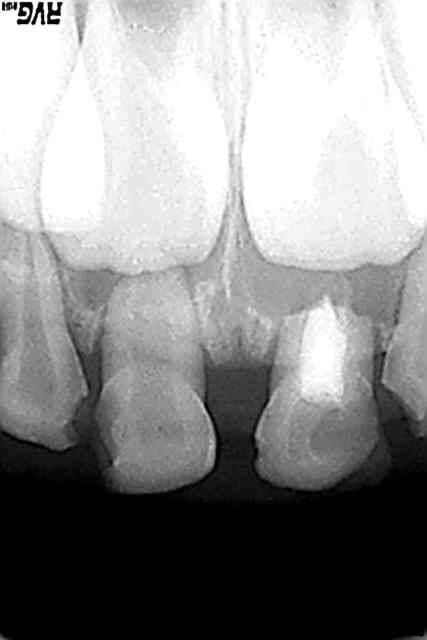

27/08/2007 à 16h44

obturation IRM:ça se resorbe...

patiente 6 ans 3mois,evolution normale si on compare à 51 non traitée